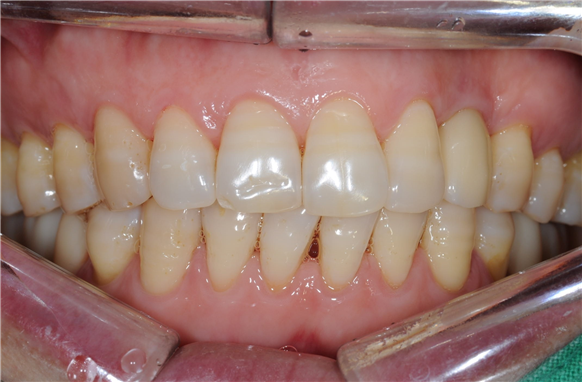

사진은 최종 치료 후 4년이 지났을 때 촬영된 사진입니다. 심미성과 기능성 모두 양호한 상태였습니다.

임플란트 수술 후에는 단단하거나 질긴 음식을 섭취할 때 앞니 사용을 자제하고, 임플란트 주위염을 막기 위해 규칙적이고 꼼꼼한 양치질이 중요합니다. 더불어 정기 치과검진을 통해 치아의 상태를 점검하면서 스케일링을 통해 구강 질환을 예방하는 것이 바람직합니다.